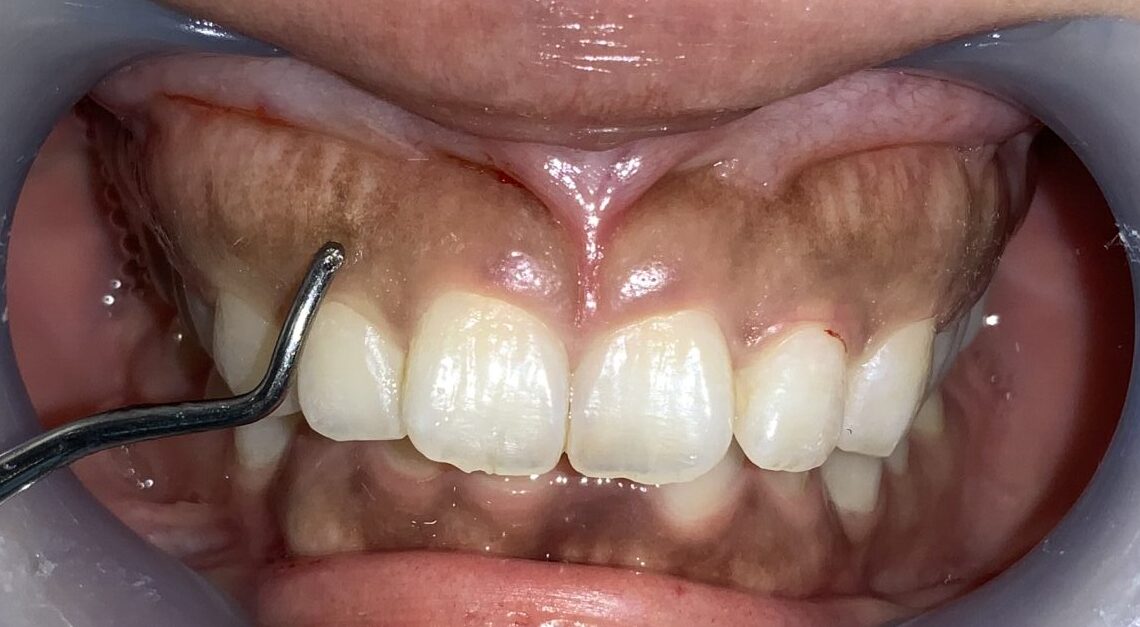

少し小さい隣の歯です。

歯ぐきは薄いようですが、歯ぐきの被っている量はたくさんあります。

今度は犬歯です。この歯は大きく切り取ってしまうと「八重歯」みたいになってしまうので、歯ぐきを整形するときに注意が必要な歯です。

歯ぐきが被っている量や厚みはたくさんあります。

前歯に戻って反対側です。

こちらも歯槽骨のざらざら感や、とがった部分がありそうです。